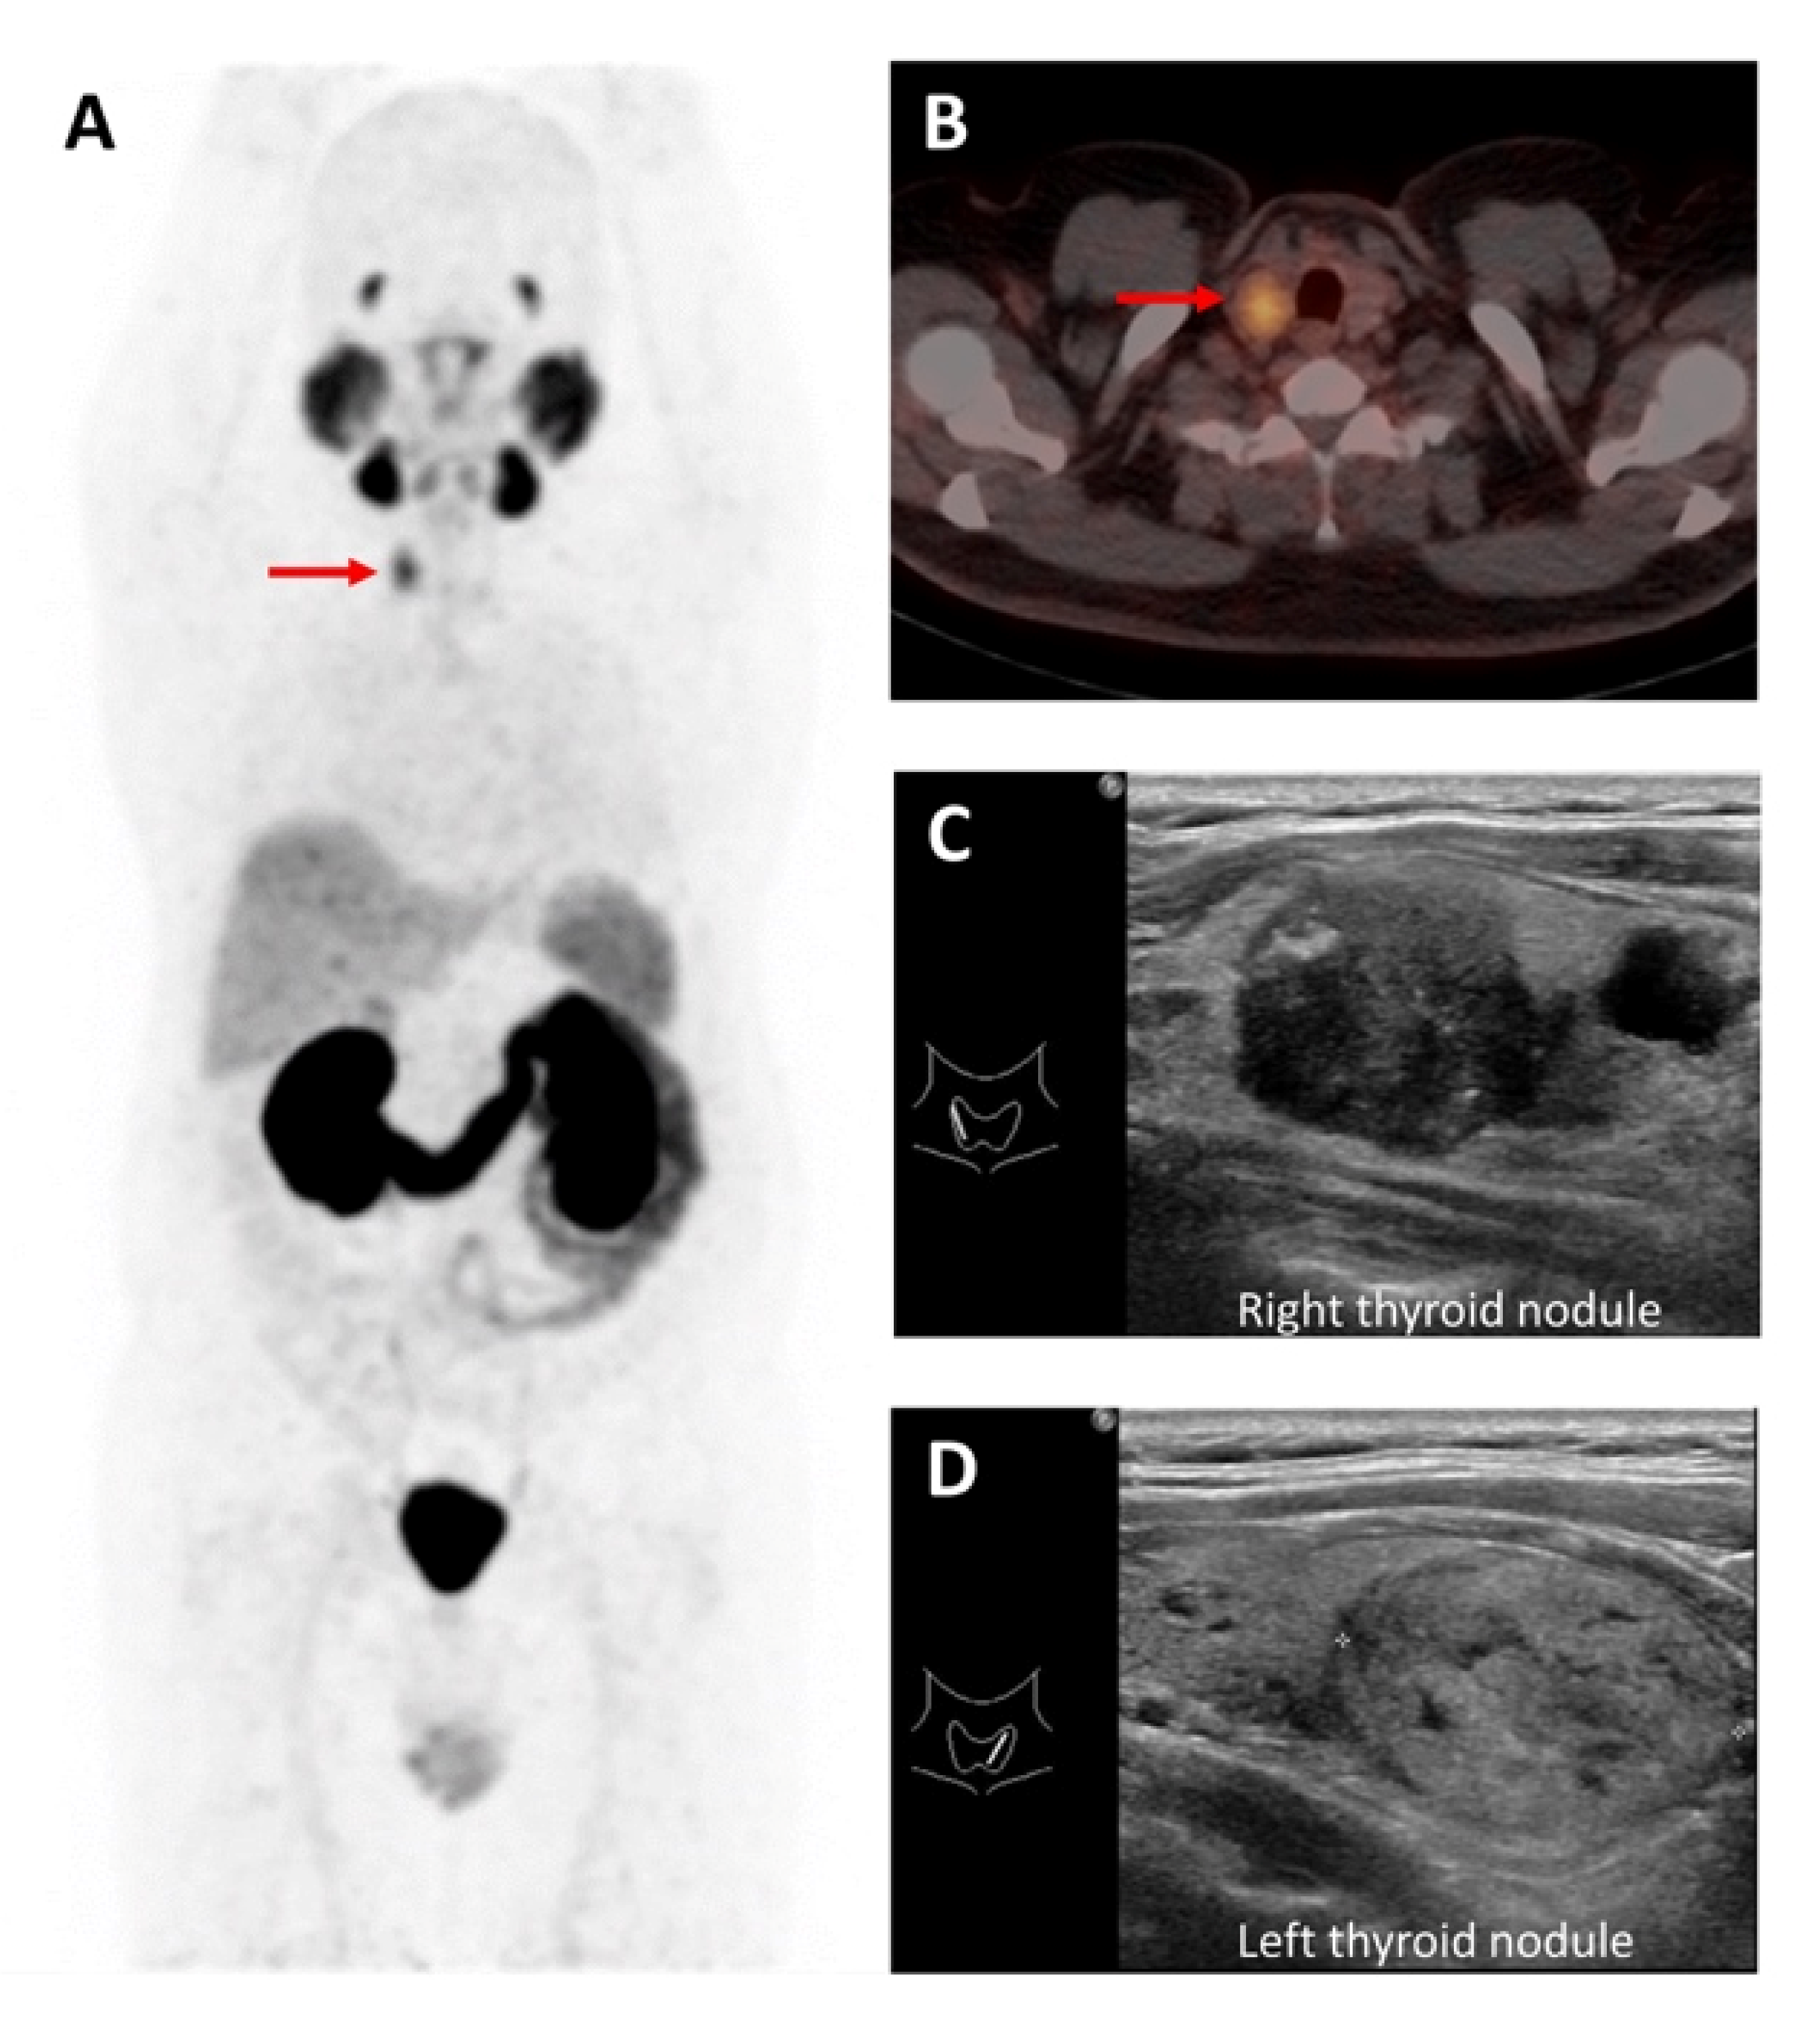

- de Leijer, J.F.; Metman, M.J.H.; van der Hoorn, A.; Brouwers, A.H.; Kruijff, S.; van Hemel, B.M.; Links, T.P.; Westerlaan, H.E. Focal Thyroid Incidentalomas on 18F-FDG PET/CT: A Systematic Review and Meta-Analysis on Prevalence, Risk of Malignancy and Inconclusive Fine Needle Aspiration. Front. Endocrinol. 2021, 12, 723394. [Google Scholar] [CrossRef] [PubMed]

- Piccardo, A.; Puntoni, M.; Bertagna, F.; Treglia, G.; Foppiani, L.; Arecco, F.; Giubbini, R.; Naseri, M.; Cistaro, A.; Cabria, M.; et al. 18F-FDG Uptake as a Prognostic Variable in Primary Differentiated Thyroid Cancer Incidentally Detected by PET/CT: A Multicentre Study. Eur. J. Nucl. Med. Mol. Imaging 2014, 41, 1482–1491. [Google Scholar] [CrossRef]